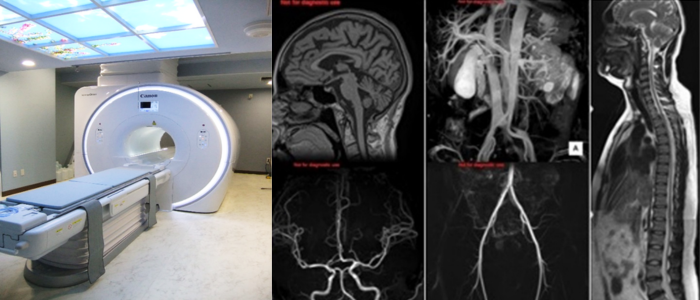

M R I撮影

・Canon Vantage Orian 1.5T

強力な磁石でできたトンネル型の装置に入り、磁気の力を利用して体の臓器や血管を撮影する事ができます。

特に脳や、脊椎、関節、腹部から骨盤内の病変に対して優れています。

また造影剤を使用しなくても血管の撮影を行うことができます。(検査によって造影剤を使用する事もあります)

放射線科の中で唯一放射線を使用しない装置であり、被ばくの心配がありませんが、撮影室内は非常に強い磁力が発生しているため、着替えや装飾品の取り外しやお化粧の制限、事前の問診にご協力を頂いています。